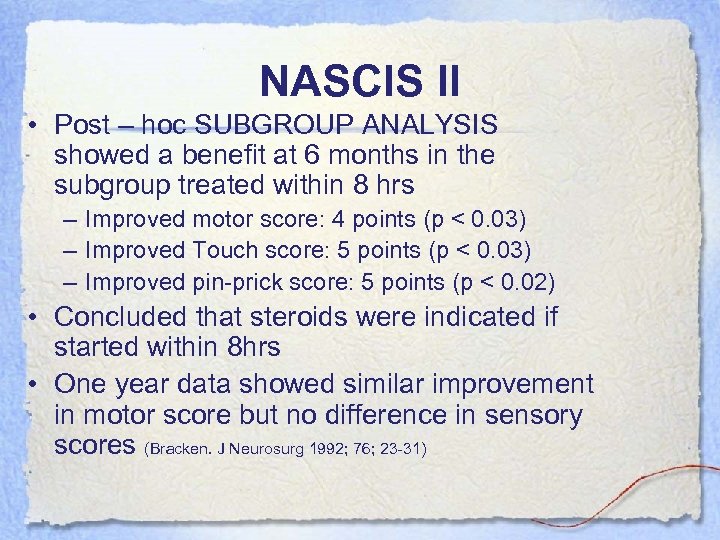

NASCIS II • Post – hoc SUBGROUP ANALYSIS showed a benefit at 6 months in the subgroup treated within 8 hrs – Improved motor score: 4 points (p < 0. 03) – Improved Touch score: 5 points (p < 0. 03) – Improved pin-prick score: 5 points (p < 0. 02) • Concluded that steroids were indicated if started within 8 hrs • One year data showed similar improvement in motor score but no difference in sensory scores (Bracken. J Neurosurg 1992; 76; 23 -31)

NASCIS II • Post – hoc SUBGROUP ANALYSIS showed a benefit at 6 months in the subgroup treated within 8 hrs – Improved motor score: 4 points (p < 0. 03) – Improved Touch score: 5 points (p < 0. 03) – Improved pin-prick score: 5 points (p < 0. 02) • Concluded that steroids were indicated if started within 8 hrs • One year data showed similar improvement in motor score but no difference in sensory scores (Bracken. J Neurosurg 1992; 76; 23 -31)